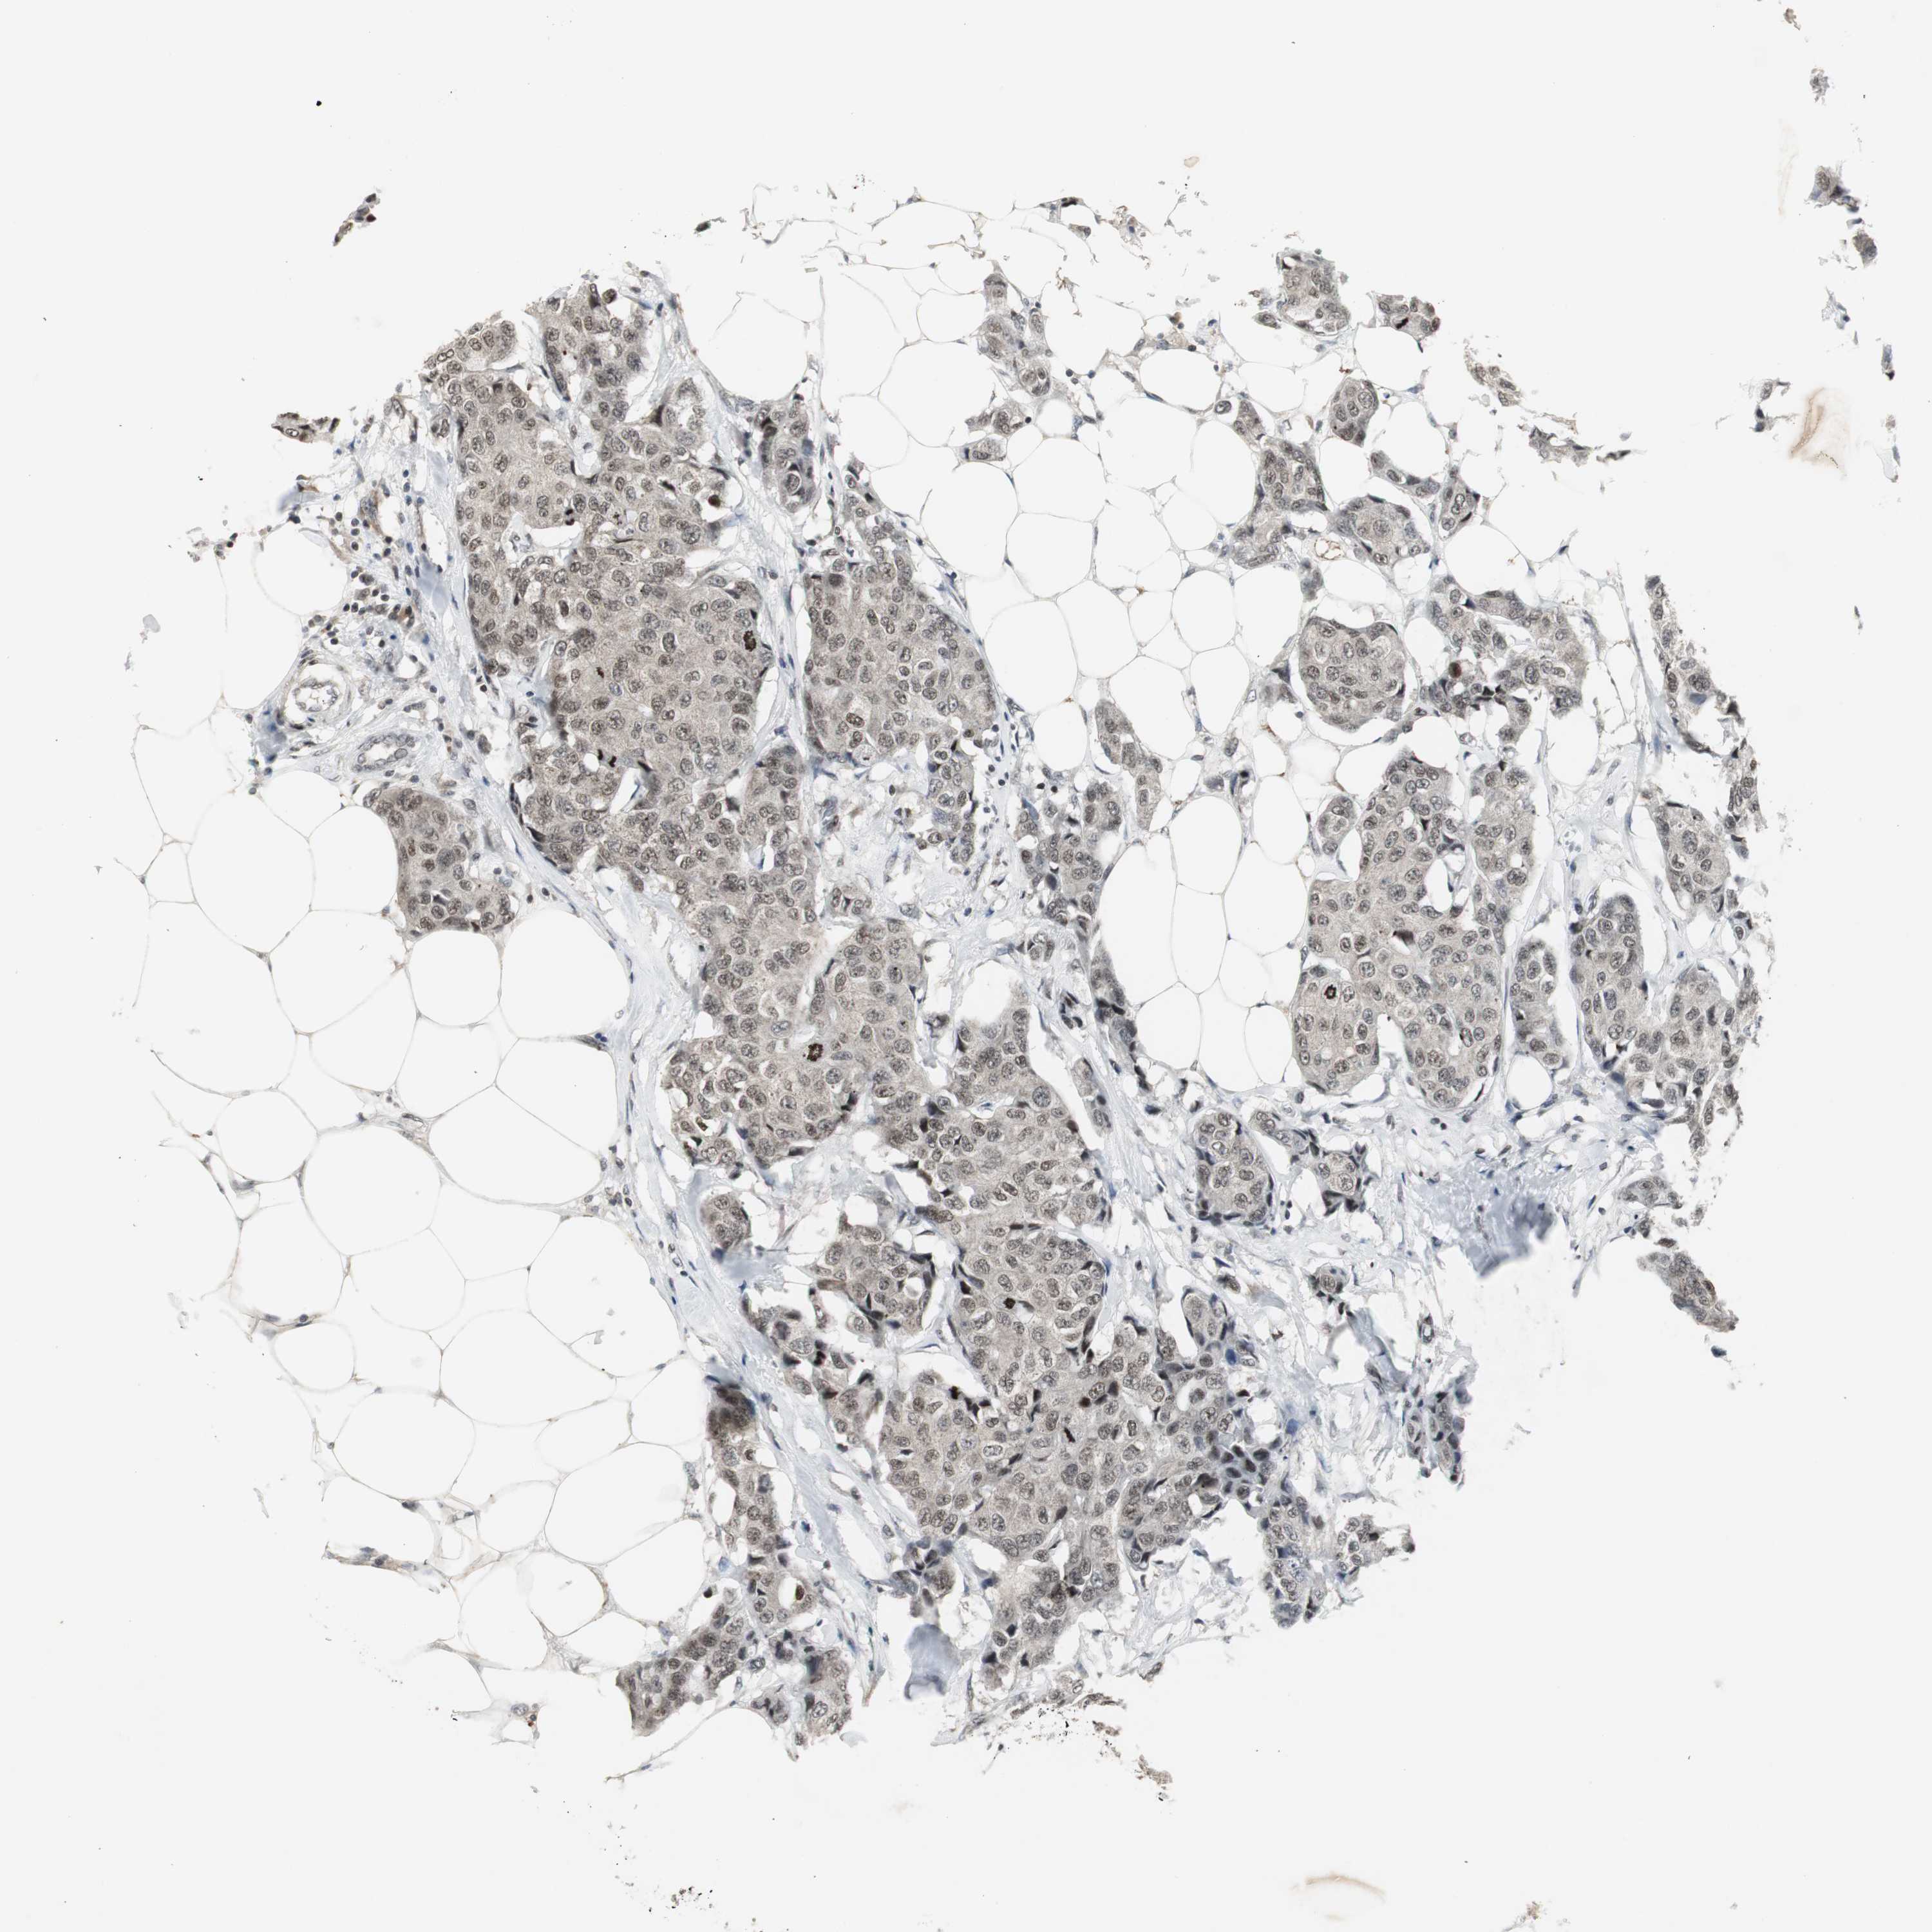

CANCER BREAST CANCER Show tissue menu

BRCA TCGA BRCA VALIDATION PROTEIN EXPRESSION

Breast cancer

Human cancer